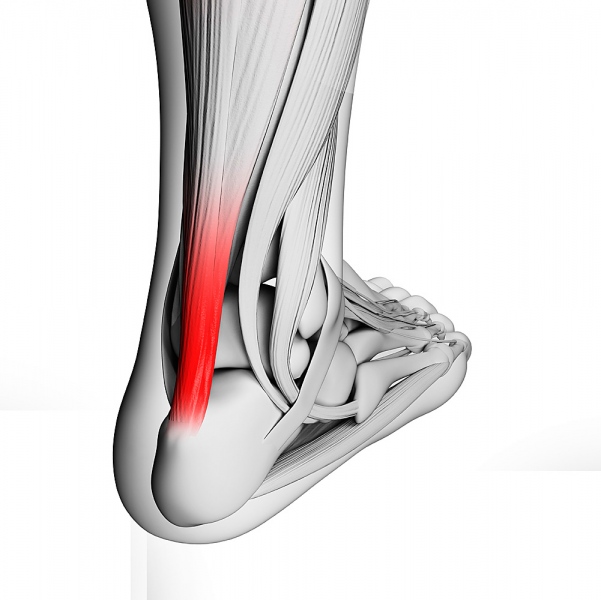

Rotura tendón de Aquiles

Rotura tendón de Aquiles La rotura del tendón de Aquiles sucede en cualquier rango de ...

Reparación de tendones

Reparación de tendones La prótesis de tobillo es una técnica quirúrgica de muy buenos resultados ...